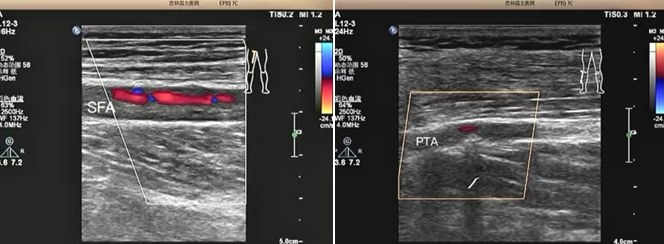

該患者是一位老年男性,因 “雙小腿麻木、發(fā)涼 2 個月” 前來我院就診。超聲科為其進行下肢動靜脈彩超檢查時,精準發(fā)現(xiàn)其股淺動脈及脛后動脈存在重度狹窄至閉塞的情況。超聲檢查憑借其無創(chuàng)、便捷的獨特優(yōu)勢,在第一時間就為臨床治療提供了準確無誤的診斷依據(jù),為后續(xù)治療方案的制定奠定了堅實基礎。

超聲檢查以其無創(chuàng)、便捷、可重復的顯著優(yōu)勢,在此次診療過程中發(fā)揮了重要作用,清晰地顯示了患者下肢動脈的病變情況:1、準確判斷病變部位:精準定位到股淺動脈及脛后動脈。2、明確病變程度:確定為重度狹窄至閉塞。3、評估側支循環(huán)建立情況:為治療方案的制定提供了關鍵參考。